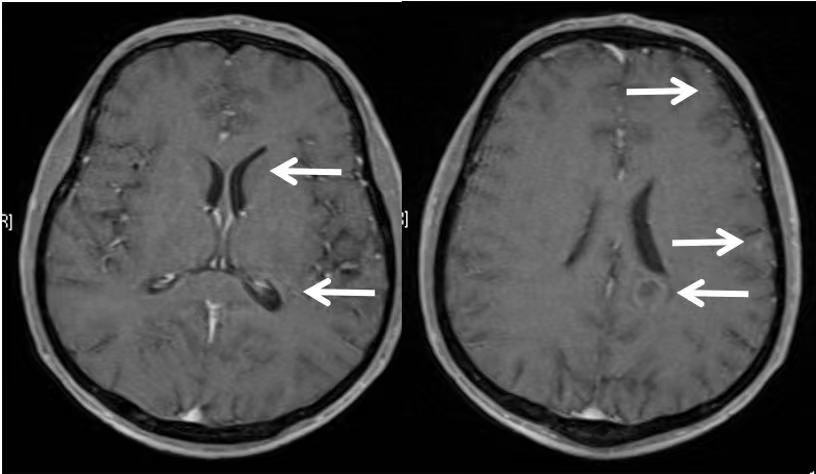

可是好景不长,同年8月,李先生在干活的时候,突然出现头晕,而且逐渐加重,并出现双下肢乏力,腿脚不灵活等症状。紧急去医院复查,做了一个头颅MR,提示:颅内多发异常信号,转移瘤可能性大。

克唑替尼耐药了!无奈,平静的生活不得不再次中断,迎接李先生的是全脑放疗。

奇迹再次发生,在放疗并配合药物治疗之后,颅内转移灶,在持续缩小!在后期的随访中,颅内的病灶一直没有再复发。